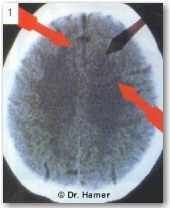

Во время второй части фазы исцеления НН проявляется на томографических снимках в виде кольца белого цвета.

На снимке виден НН в зоне мозга, контролирующей коронарные артерии, указывающий на то, что «конфликт утраты территории» был успешно разрешен.

Во время эпи-кризиса пациент успешно перенес ожидаемый сердечный приступ (после angina pectoris в КА-фазе). Если бы фаза активного конфликта длилась бы в этом случае более 9 месяцев, сердечный приступ мог бы оказаться фатальным. Зная основы ННМ, можно предотвращать подобное развитие событий заранее!